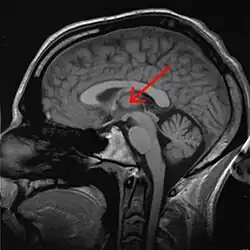

Eine weitere wichtige Region ist der Thalamus, eine Teilstruktur des Zwischenhirns. Schon Wilder Penfield erklärte 1937: „Alle Teile des Gehirns können in den normalen bewussten Prozess eingebunden sein, doch das unerlässliche Substrat des Bewusstseins liegt vermutlich außerhalb der Großhirnrinde – im Zwischenhirn.“[16] Auch wenn viele Elemente von Penfields Bewusstseinstheorie heute als veraltet gelten, spielt das Zwischenhirn – und im Besonderen der Thalamus – weiterhin eine große Rolle bei der Suche nach neuronalen Korrelaten bewussten Erlebens. Joseph Bogen etwa behauptet, dass Bewusstsein mit Aktivität in und um die unspezifischen Thalamuskerne korreliert sei.[12] Auch Gerald Edelman und Giulio Tononi betonen in ihrer Theorie die Rolle des Thalamus.[17] Allerdings ist nach ihrer Ansicht spezifische Aktivität im Thalamus alleine nicht hinreichend für bewusstes Erleben. Es habe vielmehr zwei zentrale Eigenschaften: 1) Die verschiedenen Merkmale des Erlebten werden als Einheit aufgefasst. Die Eigenschaft des Bewussten des Erlebten lässt sich nicht in Teilkomponenten aufspalten. 2) Bewusstes Erleben ist in dem Sinne differenziert, dass es möglich ist, extrem viele, sehr verschiedene Elemente in einem kurzen Zeitraum zu erleben. Nach Edelman und Tononi muss eine adäquate neurowissenschaftliche Theorie diese Eigenschaften berücksichtigen. Es sollten neurophysiologische Prozesse ausfindig gemacht werden, die sich sowohl durch vereinheitlichende Integration als auch durch Differenziertheit auszeichnen. Edelman und Tononi gehen daher von rekursiven neuronalen Prozessen aus, deren Aktivierung durch Schleifenbahnen („reentrant loops“) läuft. Der Thalamus spielt bei diesen Schleifen eine zentrale Rolle. Die Autoren vertreten dabei einen eher holistischen Ansatz. Sie erwarten demnach, dass sich keine eng umgrenzten Neuronenverbände finden lassen, die als neuronales Korrelat bewussten Erlebens gelten können. Vielmehr komme es immer auf eine sehr umfassende Aktivität in weiten Teilen des Gehirns an.